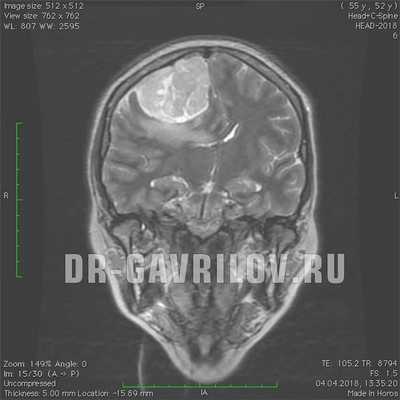

На фото МРТ менингиомы головного мозга

Наиболее информативными и точными методами диагностики менингиомы являются компьютерная томография (КТ) и магнитно-резонансная томография (МРТ). Как правило, данные исследования проводят с контрастированием. КТ и МРТ позволяют определить размер опухоли, её локализацию, степень поражения окружающих тканей и возможные осложнения.